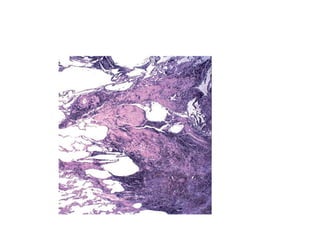

Morphology

• Occlusion of bronchi and bronchioles by

mucus plug

• Mucus plug contain whorls of shed

epithelium - curschmann spirals

• Eosinophils and charcot leyden crystals

(Crystalloid made up of eosinophil

membrane protein)

41

Airway remodeling

Is characteristic finding of asthma

Thickening of the basement membrane of

the bronchial epithelium

Edema and inflammatory infiltrate in the

bronchial walls, with prominence of

eosinophils and mast cells

Increase in size of the submucosal glands

 Hypertrophy of the bronchial muscle wall

42